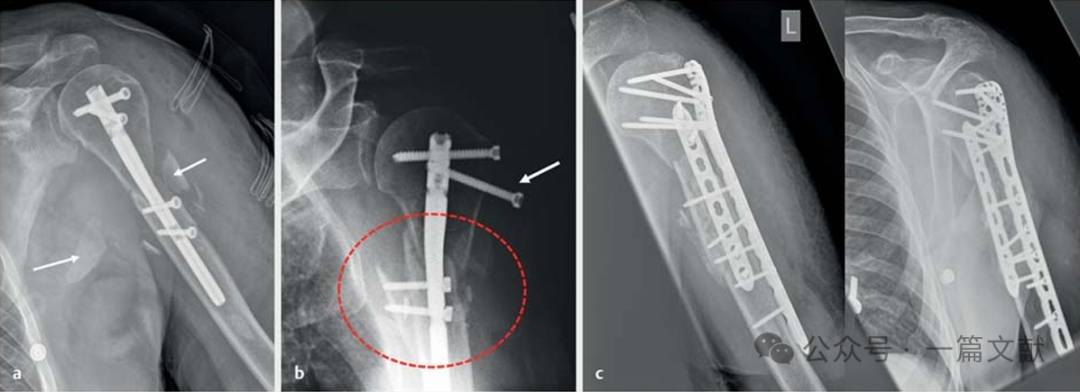

4.1 锁骨骨折的双钢板固定:常用于锁骨骨不连的翻修手术,或锁骨近端骨折的固定。如下图,

锁骨近端骨折术后8周,出现肥大性骨不连,内固定失效。

2.4,2.7mm LCP 双钢板翻修手术,10个月骨性愈合。

如下图:45岁女性,肱骨近端粉碎的内翻型骨折,外侧PHILOS钢板+前方1/3管型板固定。

4.3 肱骨干骨折:常用于肱骨干骨折骨不连的翻修手术,由于肱骨干骨折存在较大的扭转和弯曲应力,所以也经常一期应用双钢板固定技术。

如下图:42岁患者,肱骨干粉碎骨折,一期行髓内钉内固定手术,3周后骨折移位,内固定失效,予外侧PHILOS钢板+前方3.5mm LCP 固定翻修 。

29岁患者,肱骨干骨折内固定失效后,予翻修手术,拆除原钢板,清理骨折端,桡背侧3.5mm钢板+尺侧3.5mmLCP板固定。

下图为,28岁年轻人,掰手腕导致骨折,背侧入路,肱骨远端桡背侧3.5mm钢板+尺侧3.5mmLCP板固定。